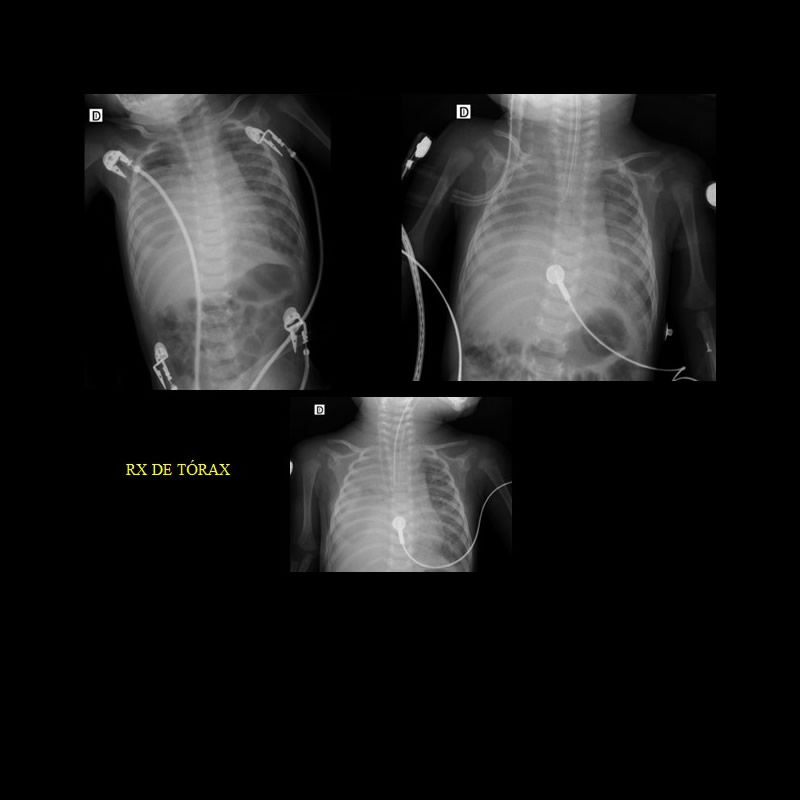

Escasa ganancia ponderal. Crisis de cianosis generalizada